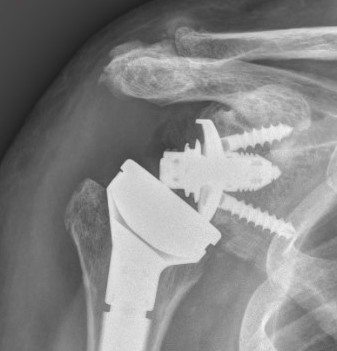

Periprosthetic fracture

Intra-operative glenoid fracture 0.4%

Reverse TSR NotchingGlenoid fracture

Humeral shaft fractures

Hum shafthum shaftHum shaft

Stable humeral component treated with ORIF

hum #Hum #Hum #

Unstable humeral component